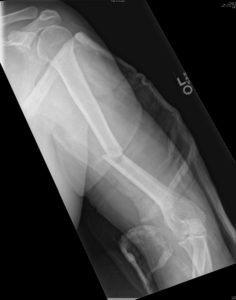

Fractures to the mid portion (shaft) of the upper arm (humerus) are not as common as fractures to the shoulder region. The humeral shaft is cylindrical in shape and serves as a point of attachment for several muscles that aid in movement of the shoulder and elbow. The radial nerve travels intimately close to the humeral shaft and fractures in this area can cause injury to the nerve. Damage to the radial nerve in this region can cause an inability to extend the wrist and fingers.

Humeral shaft fractures can be treated with bracing in many circumstances. The brace will help to hold fracture alignment while allowing function of the arm to resume. When alignment cannot be adequately held by the brace, or when a faster return to weight bearing on the arm is necessary, surgery may be performed. Surgery typically entails placing a plate and screws or a rod and screws to fix the fracture. Healing time and return to full activity are often less with surgery than with nonsurgical treatment.